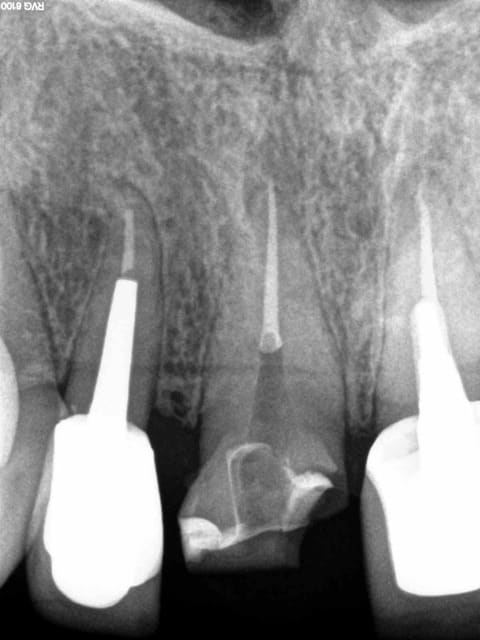

Ben quoi réduction homothétique verticale ...... et un soupçon de conicité à 6 % quand meme, mais pour la voir il faut avoir l'oeil !-)))))

Ca n'a pas trainé ! Pourtant j'étais bien parti. Septembre chicot ! -))))